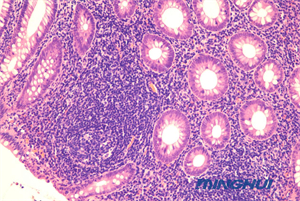

廣州明慧生物顯微鏡NE710+ MHD2000用于醫(yī)院病理檢驗(yàn)

廣州明慧科技推出的生物顯微鏡NE710與顯微鏡攝像頭MHD2000組合,廣東某醫(yī)院病理科引進(jìn)了這套設(shè)備,試機(jī)過(guò)程中,實(shí)驗(yàn)老師對(duì)這套設(shè)備的表現(xiàn)效果尤為滿(mǎn)意,圖像的高清晰度與色彩還原度,提升了病理檢驗(yàn)的準(zhǔn)確性和效率。

NE710顯微鏡采用了NIS無(wú)限遠(yuǎn)光學(xué)系統(tǒng),提供優(yōu)秀的可擴(kuò)展性,確保成像質(zhì)量。高數(shù)值孔徑(NA) 和長(zhǎng)工作距離,成像清晰度高,適用范圍廣,還原真實(shí)色彩,實(shí)現(xiàn)對(duì)樣本的準(zhǔn)確觀察。

MHD2000顯微鏡攝像頭以其2000萬(wàn)的有效像素、高分辨率和高對(duì)比度,接近目鏡的色彩表現(xiàn),USB3.0的高速數(shù)據(jù)傳輸接口,確保了圖像的高清晰度與色彩還原度,使得觀測(cè)結(jié)果更加準(zhǔn)確可靠,為病理檢驗(yàn)提供了精準(zhǔn)可靠的圖像支持。

在實(shí)際應(yīng)用中,這套設(shè)備幫助病理科準(zhǔn)確識(shí)別了多種疾病的病理特征,特別是在腫瘤和感染性疾病的診斷中,發(fā)揮了重要作用。實(shí)驗(yàn)老師表示,使用這套設(shè)備后,病理檢驗(yàn)的準(zhǔn)確性和效率都有了顯著提升。

廣州明慧生物顯微鏡NE710與顯微鏡攝像頭MHD2000的組合,以其卓越的性能和精準(zhǔn)的觀測(cè)能力,贏得老師的好評(píng),成為醫(yī)院病理檢驗(yàn)的重要工具,也為醫(yī)學(xué)研究和臨床教學(xué)提供了有力支持。